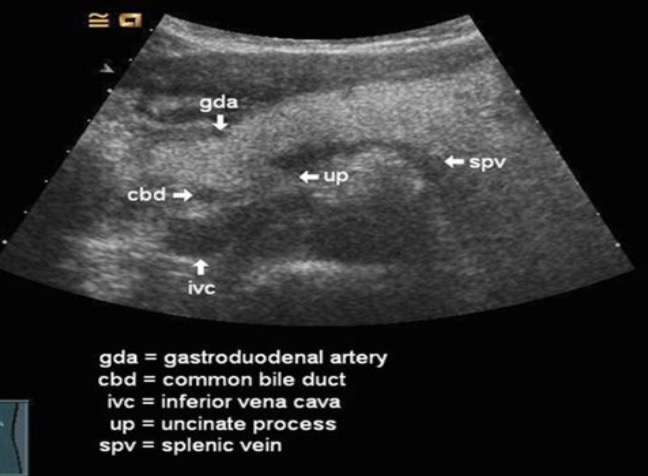

CBD in relation to pancreas

Seen at the posterior lateral margin of the pancreatic head

GDA in relation to pancreas

Can be seen at the anterior lateral margin

The SMV in relation to the ucinate process and neck and body of the pancreas

The SMV crosses anterior to the ucinate process and posterior to the neck and body of the pancreas

The uncinate process

The small, curved tip at the end of the head of the pancreas